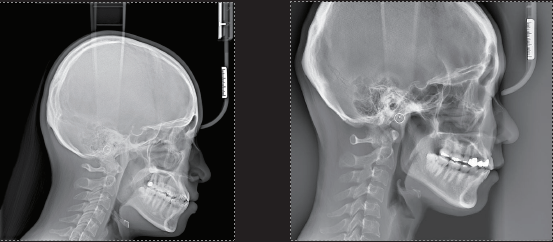

Cephalometric Options

- SC (Scanning Ceph) Max 26 x 22.5 cm

- OCS (One-Shot Ceph Standard) Max 30 x 25 cm (Optional)

- OCL (One-Shot Ceph Large) Max 33 x 33 cm (Optional)